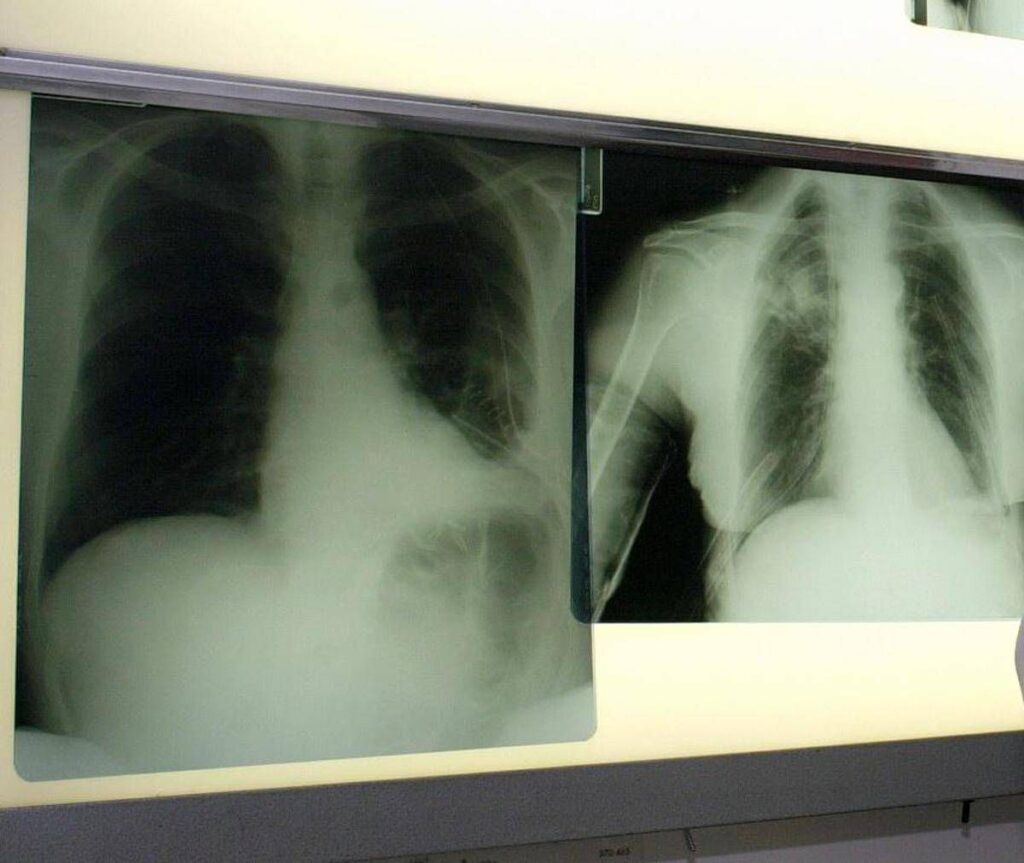

Il tumore al polmone – ricorda l’azienda in una nota – continua a essere una delle neoplasie più diffuse e letali in Italia e nel mondo. Ogni anno, solo in Italia, vengono diagnosticati 44.831 nuovi casi. Circa il 12% riguarda il carcinoma polmonare a piccole cellule, una forma aggressiva e a rapida progressione, per la quale le opzioni terapeutiche sono rimaste a lungo limitate. Negli ultimi anni, tuttavia, i progressi nel trattamento dello Sclc hanno aperto nuove prospettive. Tra questi, un composto sintetico di origine marina – estratto dall’invertebrato Ecteinascidia turbinata – che ha dimostrato risultati promettenti in combinazione come terapia di mantenimento in prima linea per i pazienti con Sclc in stadio esteso (Es-Sclc), una delle forme tumorali più aggressive e con maggiori bisogni clinici insoddisfatti. Come dimostrano i risultati dello studio di fase 3 IMforte, presentato lo scorso giugno all’Asco Annual Meeting 2025 di Chicago, il Congresso dell’American Society of Clinical Oncology, il composto sintetico di origine marina, in combinazione con immunoterapia, riduce del 46% il rischio di progressione della malattia o di morte, con una sopravvivenza mediana globale di 13,2 mesi rispetto ai 10,6 mesi con la sola immunoterapia.